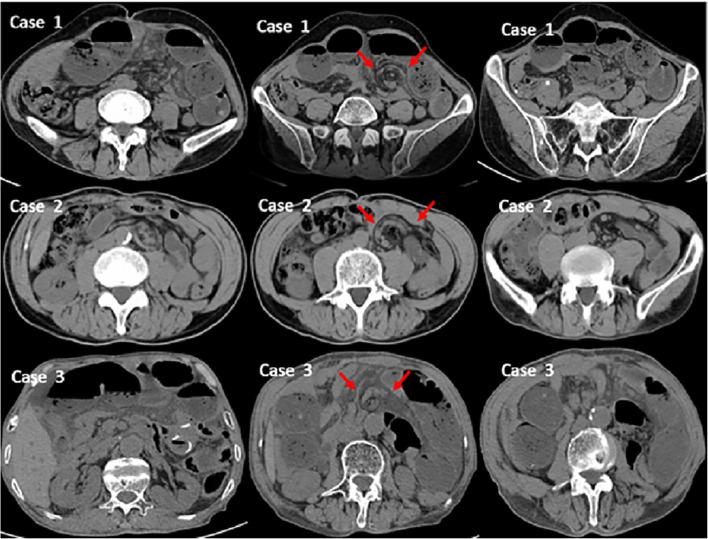

Petersen's hernia (PH) is a serious complication after gastrectomy for gastric cancer. The aim of this study was to investigate whether closure of Petersen's defect (PD) can decrease the rates of PH and suspected Petersen's hernia (SPH).

Patients who underwent gastrectomy with PD were enrolled. From January 2014 to January 2017, we performed gastrectomy without PD closure (non-closure group). From February 2017 to June 2018, we closed PDs during gastrectomy (closure group). The rates of PH and SPH were compared between the two groups. The last follow-up was updated in August 2020.

Among a total of 1213 patients, 12 patients (1.0%) developed PH, and 23 patients (1.9%) developed SPH. The rate of PH in the closure group was significantly lower than that in the non-closure group (1/385, 0.3% versus 11/828, 1.3%, p = 0.042, log-rank test). The rate of SPH in the closure group was significantly lower than that in the non-closure group (1/385, 0.3% versus 22/828, 2.7%, p = 0.008, log-rank test). Non-closure of PD was a risk factor for PH and SPH (odds ratio (OR) 7.72, 95% CI 1.84-32.35, p = 0.006).